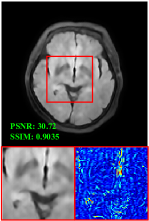

Figure 5 provides the qualitative comparison of the various methods on the four datasets at a scale of 4. The top, second, third, and bottom rows are the SR results under the FastMRI, clinical brain, clinical tumor and clinical pelvic datasets, respectively. The red boxes indicate the zoom-in region of complicated anatomical structures along with their corresponding error maps. Note that the brighter textures in the error maps, the lower the quality of the reconstructed images. As can be seen, compared to methods based on Transformers and CNNs, diffusion-based methods like DisC-Diff and DiffMSR (Ours) are capable of reconstructing high-realistic images with promising reconstruction metric scores (PSNR and SSIM). Nevertheless, while DisC-Diff can reconstruct high-precision MR images, it does not preserve the structure present in the original HR images, introducing some additional information that can affect medical diagnosis. In contrast, our method combines DM and PLWformer, which can preserve the original image’s structure while restoring high-frequency information.

Effect of Condition. To evaluate the effect of the condition extraction module, we design a variant by removing CE (named as w/o CE), which means that condition is not employed in the denoising process, as shown in Table 2. As can be seen, without condition , the reconstruction performance decreases, which demonstrates that condition extracted by the CE can provide supplementary information for the denoising network. Besides, Figure 6 provides a qualitative comparison w/o CE. As can be seen, without condition , the reconstructed image will lose some complicated anatomical structures.

In this section, we present more visual qualitative comparisons. Figures 8, 9, 10, and 11 show the reconstruction results of each method in FastMRI, clinical brain, clinical tumor, and clinical pelvic, respectively. As can be seen, although DisC-Diff can reconstruct MR images with high-frequency information, it fails to preserve the structure and content of the original Target HR image effectively, resulting in image distortion. In contrast, our proposed DiffMSR can restore high-frequency information while preserving the structure of the original HR image, indicating the effectiveness of the joint use of DM and PLWformer.